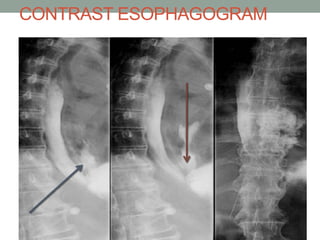

CONTRAST ESOPHAGOGRAM